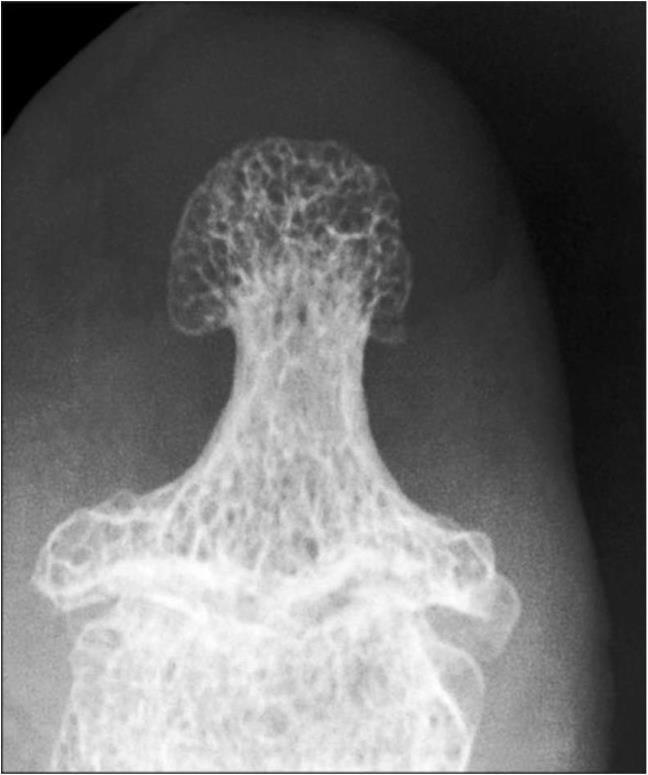

IV стадия — резко выраженная деформация эпифизов, более значительная в суставной впадине, значительное неравномерное сужение суставной щели с возможным разрушением кортикального слоя эпифизов, подвывихами суставов. В IV стадии деформация эпифизов более значительна в суставной впадине. Крупные разрушенные остеофиты окружают суставную поверхность. Расположены остеофиты в основном по тыльным и боковым поверхностям фаланг, в меньшей степени — по ладонной плоскости. Смежные отделы костей склерозированы, с множественной кистовидной перестройкой как по периферии, так и по оси сустава. Суставная щель значительно неравномерно сужена (рис. 9, 10).

Рис. 9. Рентгенограмма дистального межфалангового сустава IV пальца правой кисти больного с IV стадией первичного остеоартроза

Прямое 7-кратное увеличение рентгеновского изображения. Значительное неравномерное сужение суставной щели. Расположенный отдельными участками субхондральный склероз, эностоз. Множественная кистовидная перестройка. Резко выраженное разрастание окостеневающей хондроидной ткани — остеофиты